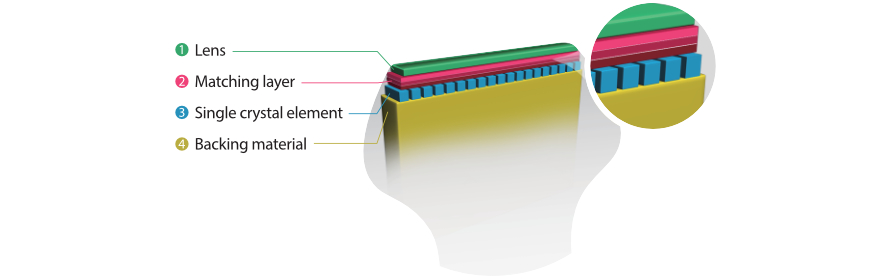

3T Transducer Technology with Single Crystal

Providing sharper images, all probes compatible with the M9 come equipped with MindrayŌĆÖs unique 3T transducer technology. Enhanced with the addition of single crystal technology, M9 offers better penetration and color dynamic flow, especially during difficult-patient scanning.